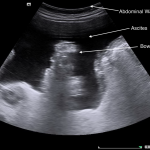

ABDOMINAL ULTRASOUND

Key features of ascites seen in this imaging modality are:

- Anechoic nature: ascites will allow sound waves to pass through it, so it will appear black/dark on ultrasound.

The gallery below organizes examples of how ascites will appear on abdominal ultrasound. Click on the thumbnails below to open up the gallery: